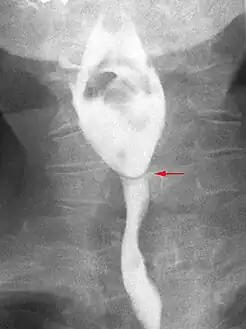

- Esophageal web stenosis in barium swallow examination lateral view.

- Esophageal web stenosis in barium swallow examination frontal view.

The diagnostic test of choice is a barium swallow.